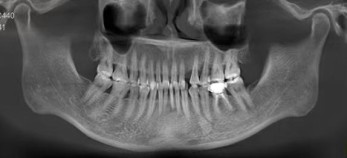

患者是一位37岁的女性,左上尖牙已缺失3年,并寻求种植修复。在此之前,患者咨询过许多医生,一直犹豫不决,最后带着疑问找到了我。

(术前CT)CT检查显示尖牙区牙齿缺失

1. 由于解剖结构的限制,尖牙区邻牙间隙较窄,且靠近重要解剖结构,这要求术者必须进行非常精准的种植,对技术要求很高。

3. CBCT显示:水平骨量不足3.5mm。